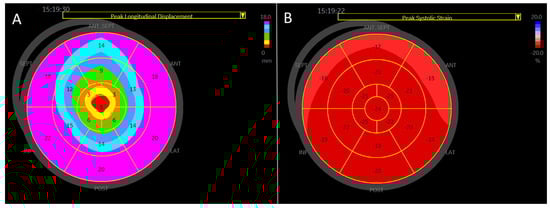

Peak longitudinal displacement was highest in the inferior and posterior segments, while it was lowest in the antero-septal wall (Table 3, Figure 4).

Peak longitudinal strain was highest in the inferior wall (Table 3, Figure 4).

Figure 4. Regional peak systolic strain and longitudinal displacement of the left ventricle in a healthy study population [Group 1]. AS—antero-septal wall, S—septum, I—inferior wall, P—posterior wall, L—lateral wall, and A—anterior wall. Longitudinal displacement is highest in the inferior and posterior wall and lowest in the anterior septum. Longitudinal strain is highest in the inferior wall.